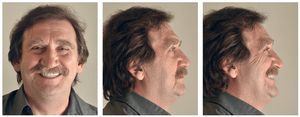

Figs. 122 a 124. La situación final extraoral.